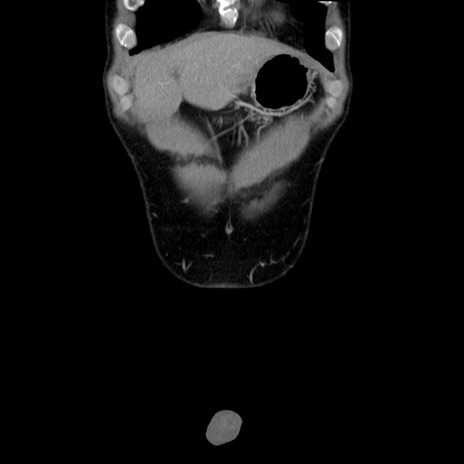

症例36(冠状断像)

【症例】20歳代 男性

【主訴】心窩部痛

【現病歴】今朝より上腹部痛あり。一旦軽快していたが再度出現したため救急要請。昨日夕に白身の魚を含む刺身を食べた。

【身体所見】BP 136/89mmHg、HR 74/min、BT 37.0℃、腹部:膨満、軟、心窩部に圧痛あり。反跳痛なし、筋性防御なし、腸雑音やや亢進あり。

【データ】WBC 17700、CRP 0.48